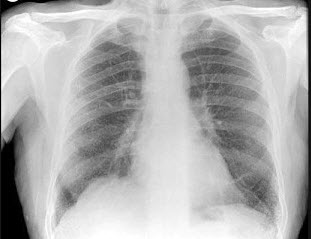

59、单项选择题

男,36岁,体检胸片如图,最可能的诊断是()

A.畸胎瘤

B.胸腺瘤

C.淋巴瘤

D.胸内甲状腺肿

E.脂肪瘤